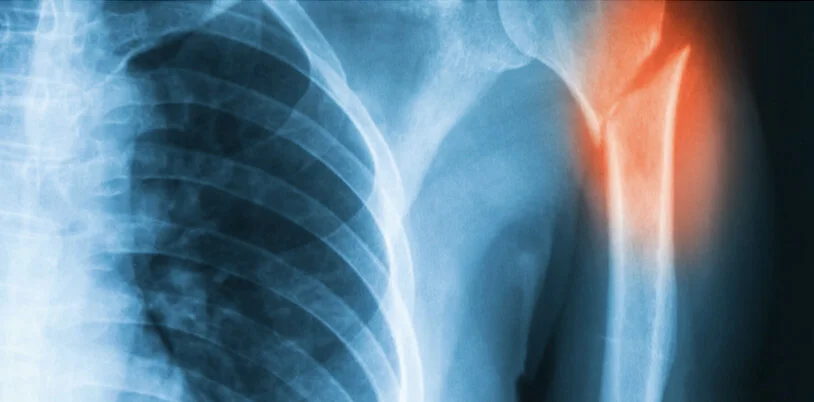

Proximal Humerus Fracture | Shoulder Surgery in Bournemouth and Poole, Dorset

Proximal Humerus Fracture.